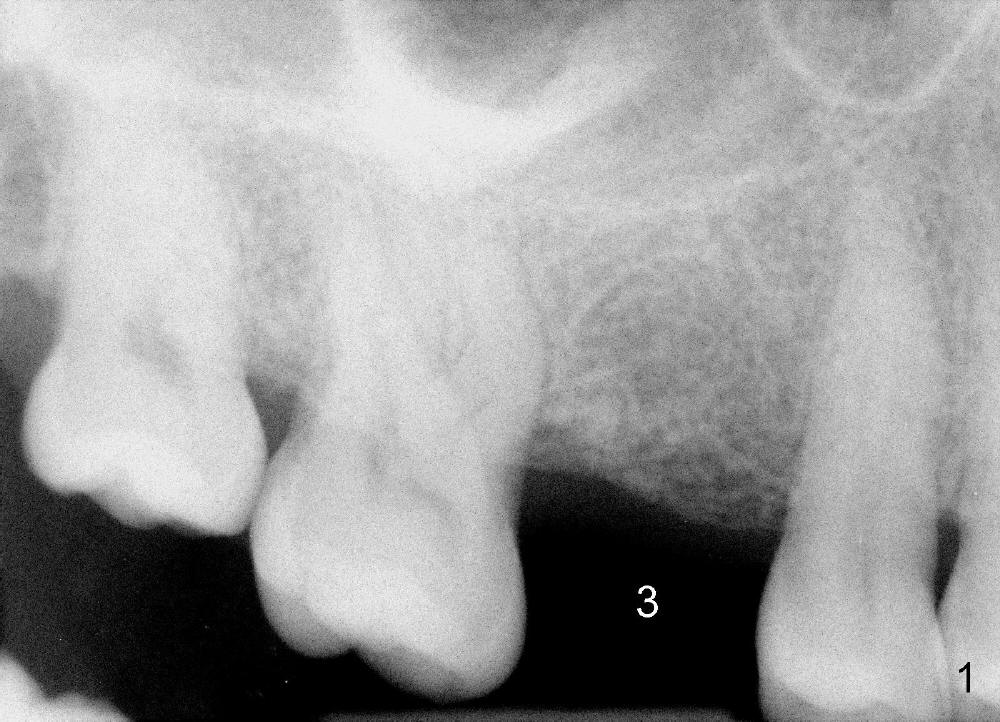

The 42-year-old lady is a dental phobic. The tooth #3 (residual root) is extracted 3.5 years ago. Finally she returns for implant (Fig.1). The mesiodistal space allows to place a 5x14 mm implant (Fig.2). Bone density is felt low when a 1.6 mm pilot drill is used. Bone condensation proceeds with bone expanders 2.6 mm (Fig.3) to 3.8 mm (Fig.4) 12 mm deep. Bone density is felt to increase with each larger expanders. When a 4x11 mm implant is placed (Fig.5), the insertion torque is 15 Ncm. When the diameter and length of the implant increase (Fig.6), the insertion torque is >60 Ncm. To have primary stability, the implant should be two sizes larger than the last expander (compare Fig.4,6)! In addition, the majority portion of the expanders is cylindrical (Fig.3,4), whereas the implant is tapered (Fig.5,6).